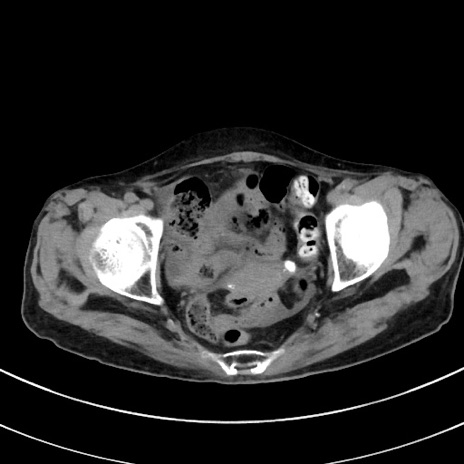

冠状断像

【症例】70歳代 女性

【主訴】心窩部痛

【現病歴】延髄病変の精査・加療にて神経内科入院中。本日より心窩部痛あり。

【既往歴】虫垂炎

【身体所見】右下腹部を中心に圧痛と反跳痛あり。

【データ】WBC 10900、CRP 0.02